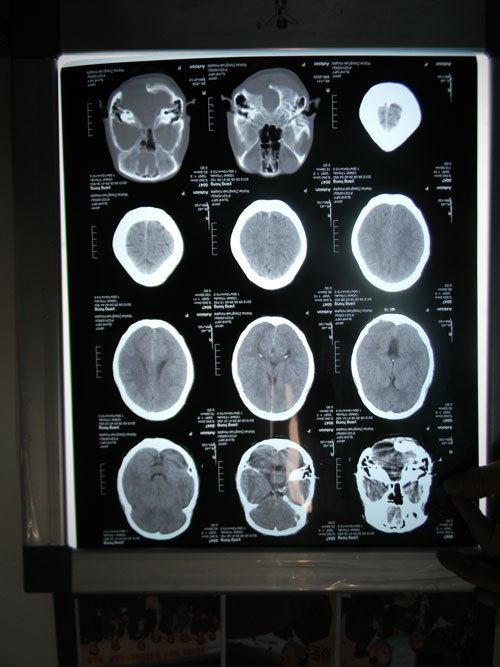

2.CT扫描:十分重要的手段,可以显示血肿、挫伤、水肿的存在及范围,也可看到骨折、积气等,必要时可多次动态扫描,以追踪病情变化。但后颅窝部位常有伪影干扰,显像欠佳。